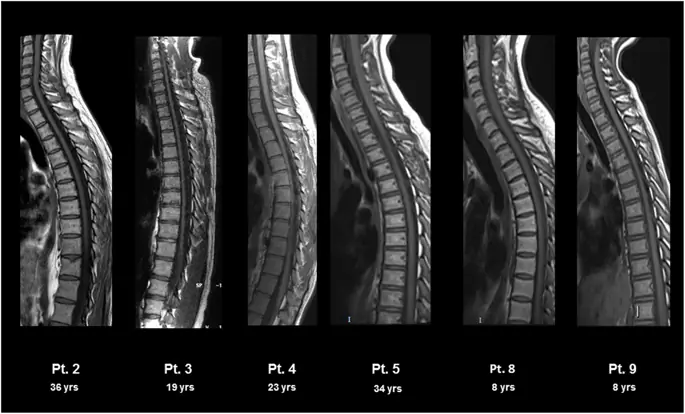

Нейрорадиологические результаты в спинном мозге показаны на рис. 3. Атрофия спинного мозга была обнаружена у 3/7 пациентов (таблица 4). У одного пациента (№ 3) нейрорадиологические особенности соответствовали особенно тяжелым клиническим и нейрофизиологическим результатам.

Рисунок 3

МРТ спинного мозга у пациентов с синдромом ХГЧ. МРТ спинного мозга, взвешенная по T1, показала атрофию различной степени (тяжелая у пациентов № 3, умеренная у пациента № 2, легкая у пациента № 4 и отсутствующая у пациентов № 5, 8 и 9)

Изображение в полном размере

Что касается спинного мозга, изменения МРТ предполагают корреляцию с клиническим исходом, причем наиболее тяжелая атрофическая дегенерация наблюдается у пациентов с более высоким баллом SPRS (пациент № 3, привязанный к инвалидной коляске, и пациент № 2, который едва поддерживает автономную походку, только для несколько шагов). Хотя скорость прогрессирования атрофии спинного мозга не может быть определена, поскольку пациенты прошли одно исследование МРТ, продолжающаяся тенденция нейрофизиологических оценок предполагает аналогичную эволюцию.